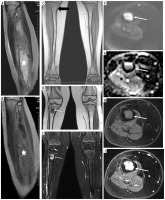

Figure 2

A 10-year-old patient (No. 38) with osteosarcoma of the left femur (thick white arrows). A) T1-weighted coronal image before, and B) after contrast medium administration, C) STIR coronal image. Thin black arrows indicate an intramedullary nail, placed as part of the first treatment of a pathological fracture At the age of 11 years brain imaging was performed due to headache and dizziness and a metastasis was suspected although atypical (thin white arrows) – a single enhancing lesion. D) T1-weighted axial image before, and E) after contrast medium administration, without strong diffusion restriction (G – DWI sequence). Very small edema around the lesion (F – FLAIR coronal image, H – T2-weighted axial image) may be due to treatment with mannitol which was implemented after the preceding CT; the same might have caused an unusual peak on proton MR spectroscopy at 3.8-3.9 ppm (I). Attention is drawn to the unreduced peak of N-acetyl-aspartate (NAA) and the unincreased choline (Cho) peak. Pathological diagnosis was pilocytic astrocytoma